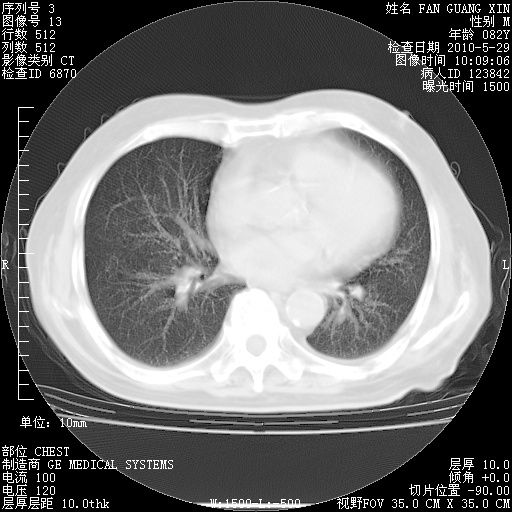

再治疗10天后的肺部CT